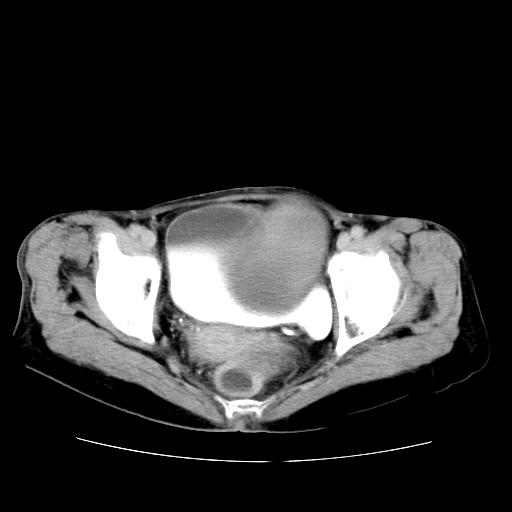

女性,72岁。

主诉下腹部坠痛不适1年余。

子宫增大如孕3月大小,质软,活动可,无压痛。

b超提示:盆腔(子宫前方)低回声团块。

临床诊断:盆腔肿块查。

1、这个肿瘤密度均匀,增强后轻中度均匀性强化,与左侧附件关系密切,肿瘤边缘光整、清晰。

2、左侧卵巢增大呈8×8×10cm大小,实性,表面光滑,边清,左侧输卵管爬行于左卵巢上,子宫萎缩。右输卵管、卵巢萎缩。

左侧卵巢纤维瘤(性索间质肿瘤)

卵巢纤维瘤为良性卵巢性索间质肿瘤,常为单侧发病,当合并腹水或胸腹水时称麦格斯(meigs)综合征,肿瘤切除后胸腹水可消失。ct表现为盆腔内边界清楚的圆形或椭圆形肿块,常有分叶或不规则;肿瘤多为实性,少数为囊性、囊实性,完全囊性者可见壁结节。实性部分与子宫等密度;增强扫描常为轻度强化或几乎不强化。